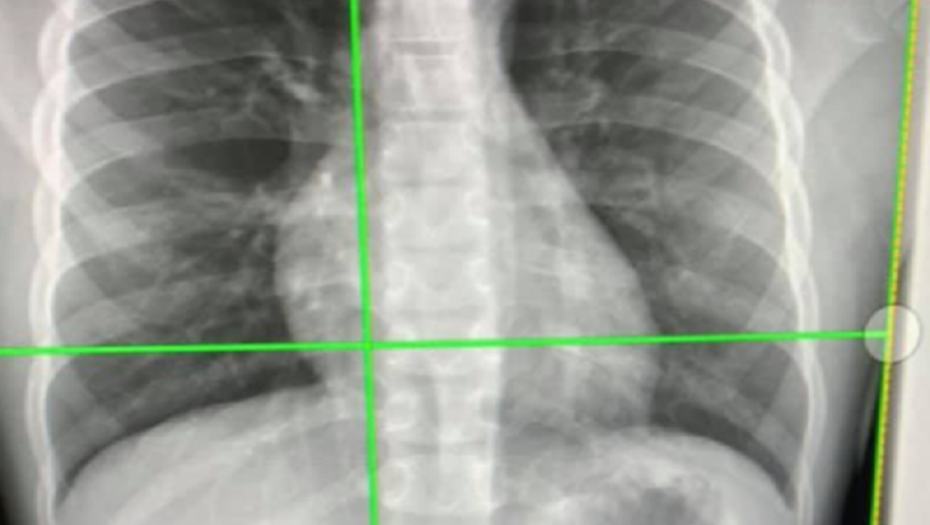

Kada je dečak stigao u dečju bolnicu u Atlanti u Džordžiji, doktori su uradili rendgen koji im je omogućio da vide bežičnu slušalicu odmah ispod njegovog grudnog koša. Rekli su porodici da puste da slušalica prirodnim putem izađe iz dečakovog tela.